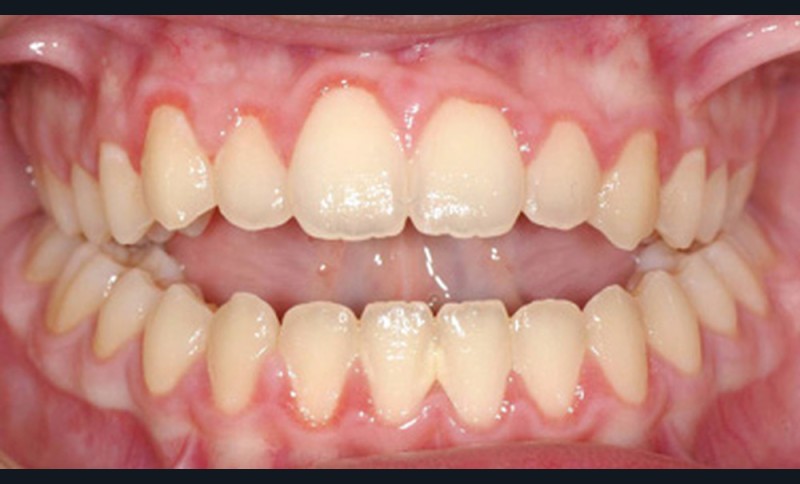

Quelques années plus tard, au moment de démarrer sa prise en charge orthodontique, la patiente présentait à nouveau une béance antérieure, un décalage des milieux incisifs de 2 mm et le problème transversal avait récidivé. Lors de l’examen clinique, elle présentait un inversé d’occlusion bilatéral postérieur et une ventilation buccale exclusive. À la suite du refus de réaliser l’amygdalectomie de façon précoce, elle ronflait toujours et sa déglutition ne s’était pas modifiée malgré des séances d’orthophonie (fig. 7 à 15).